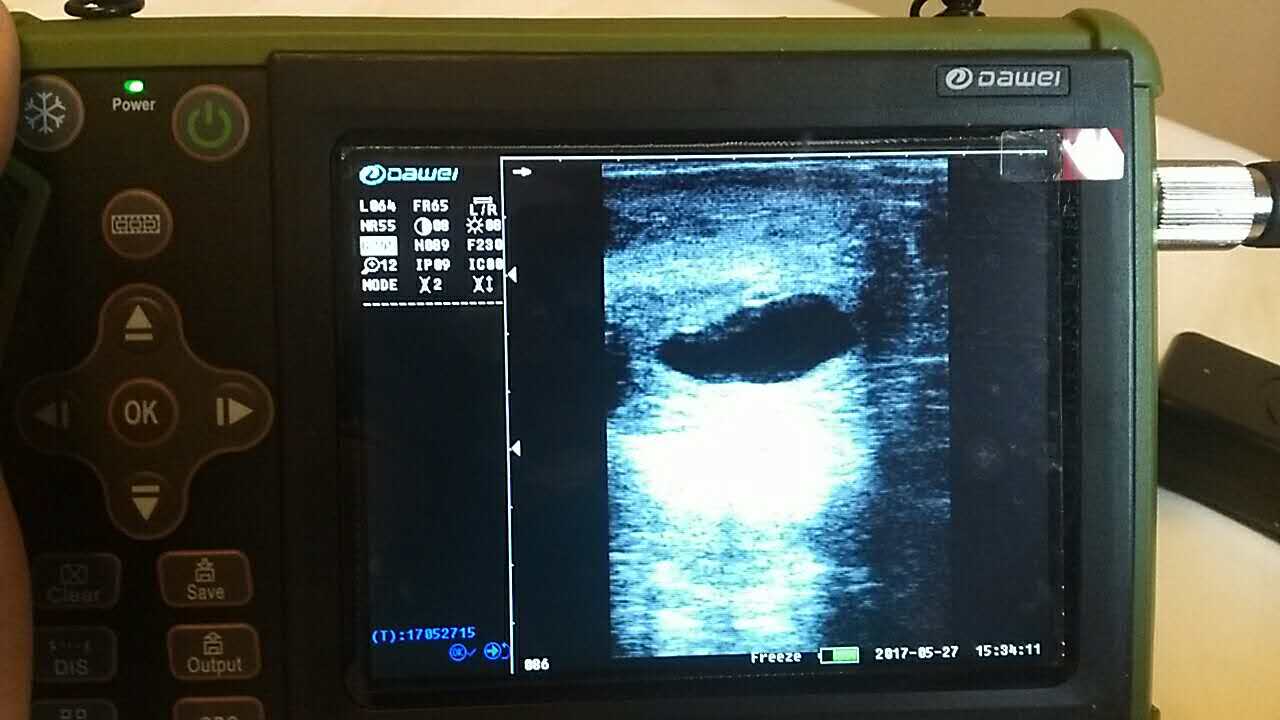

| 羊場母羊照B超辨受孕促增產(chǎn) |

養(yǎng)殖基地140只生產(chǎn)母羊集體接受了B超檢查,利用現(xiàn)代化技術(shù)方法,解決生產(chǎn)母羊繁育難題促進(jìn)畜牧業(yè)生產(chǎn)結(jié)構(gòu)的調(diào)整。 在檢查中,技術(shù)人員拿著B超儀器,給生產(chǎn)母羊做免費(fèi)受孕普查。用B超檢測母羊受孕情況,用這種方法給母羊做檢測可以準(zhǔn)確掌握母羊是否受孕、母羊生產(chǎn)周期。通過B超早期孕檢和生殖系統(tǒng)疾病診斷,可以清晰的觀測到生產(chǎn)的宮腔和胎兒的生產(chǎn)發(fā)育情況。除了幫助基地對問題羊做出正確診斷,提出合理的治療方案,淘汰無治療價值的長期空懷羊,還能提高受孕率,降低飼養(yǎng)成本,有效規(guī)避了假妊娠造成的經(jīng)濟(jì)損失。

檢測懷孕 估測胎仔數(shù) 疾病診斷 胎兒活力鑒定 胎心搏動 適用對象:適用于羊、豬、狗等動物受孕診斷(集成6種常見動物孕周測量數(shù)據(jù)包) 適用范圍:規(guī)模化豬場,人工授精站,飼料/獸藥經(jīng)銷商及企業(yè),科研教學(xué)單位 |